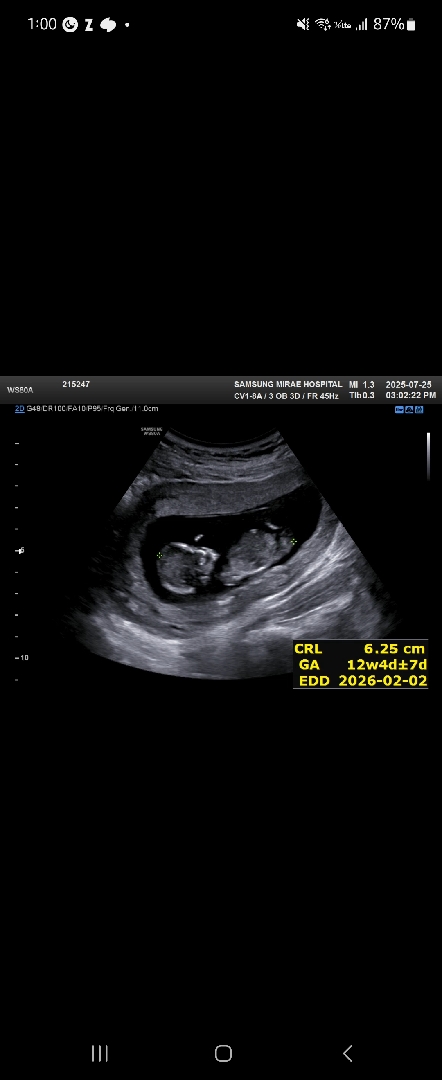

12주 4일차 각도법 봐주세요☺️

12주 4일차인데 딸일까요 아들일까요?☺️